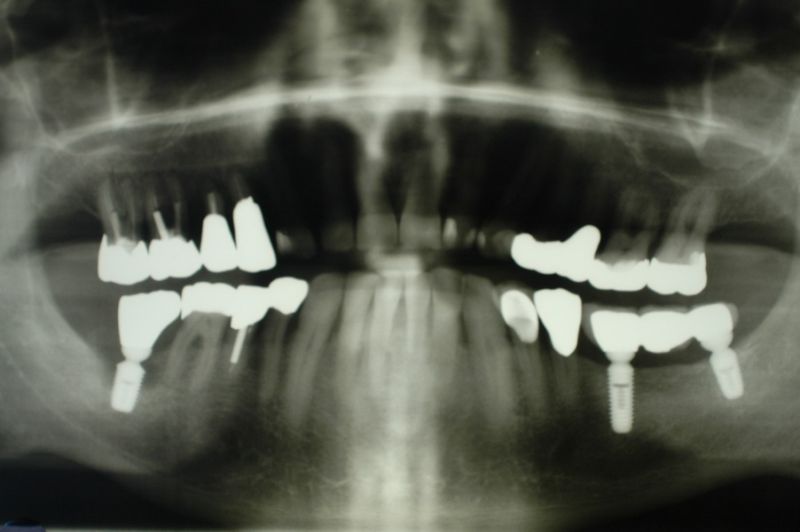

Vor ca. 20 Jahren wurde der Patient umfassend funktionstherapeutisch versorgt. Bereits zum damaligen Zeitpunkt waren die Zähne des Patienten vorgeschädigt und es lag eine Parodontalerkrankung vor.

In der Zwischenzeit sind vorgeschädigte Zähne verloren gegangen und wurden zum Teil durch Implantate ersetzt.

Über eine mehrjährige Phase wurden immer wieder Laborgefertigte Dauerprovisorien eingegliedert, weil vor einer abschließenden funktionstherapeutioschen Behandlung erst noch andere Problemzonen beseitigt werden mussten.